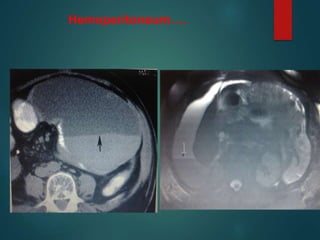

Hemoperitoneum….

• #61 Hemoperitoneum. Hematocrit level.